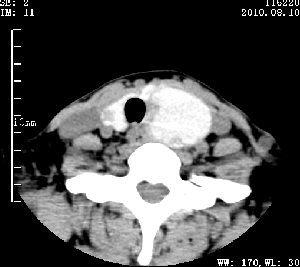

标题: CT28317:病人近几天无意间发现颈部肿块。 [打印本页]

标题: CT28317:病人近几天无意间发现颈部肿块。

甲状腺左叶局限性结节性甲状腺肿可能。建议增强扫描。

病变边界清楚,周围间隙清晰,甲状腺左叶(甲状旁腺?)肿大,右叶甲状腺腺瘤。

病变边界清楚,周围间隙清晰,左叶甲状腺肿大,右叶甲状腺小腺瘤。